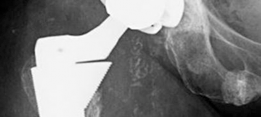

History of presenting complaint : Presents with a draining wound and well-fixed cementless components with a constrained liner due to absent abductor mechanism (Fig. 19.12). Treated with Prostalac and six weeks of IV antibiotics (Fig. 19.13). At the 6-week point, the patient sustained a ground level fall with an acetabular fracture and displacement of the acetabular Prostalac (Fig. 19.14).

Fig. 19.12 AP X-ray right THA with well-fixed components and severe osteoporosis with healed inferior pubic ramus fracture